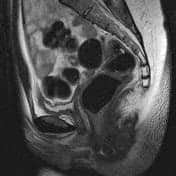

Uterus didelphys:

- Complete duplication of uterine horns as well as duplication of the cervix, with no communication between them.

- Complete failure of mullerian duct fusion

- Uterus didelphys(IOC): 2 separate endocervical canals open into separate fusiform endometrial cavities, without communication between the two horns. Each endometrial cavity ends in a solitary fallopian tube.